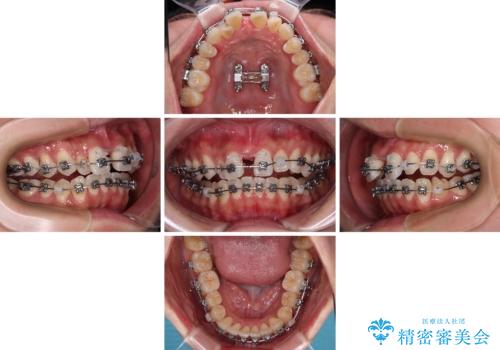

- メタルブラケット

- 1年4ヶ月

上顎歯列が下顎の歯列に対して狭小であり、一部下顎の奥歯が上顎よりも外側に位置している状態でした。

上顎の急速拡大装置を使用して上顎骨を側方に拡大することで上顎歯列を拡大し、下顎歯列も拡大できるようにすることで、歯列を整えることとしました。

歯列矯正では基本的に骨格を改善することはできませんが、急速拡大装置(MARPE)を使用することで上顎骨を側方に拡大させることができ、咬合状態を大きく改善することができます。